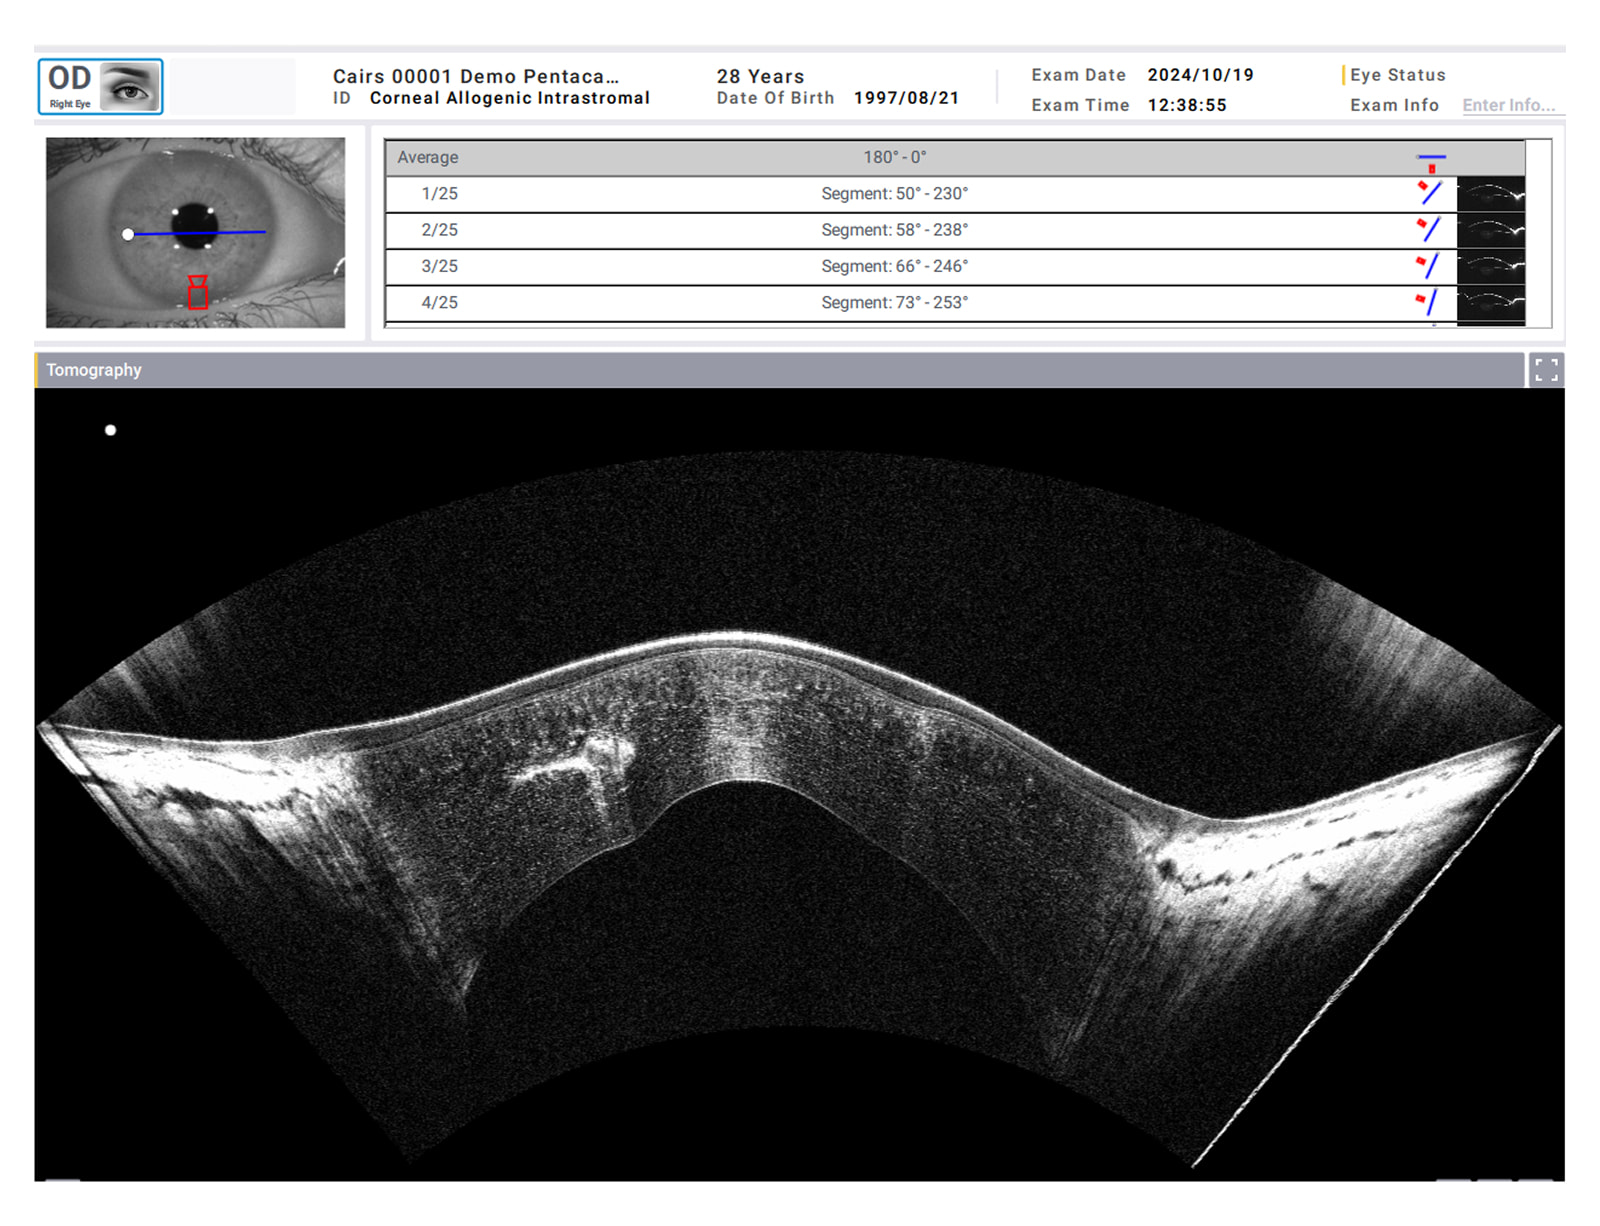

「Scheimpflug画像 + 正常眼データ + 角膜OCT画像」の組み合わせで、最適な診断をサポートします

Real shapeモードでは、角膜の実際の形状に基づいて、Bスキャン画像を再現します。角膜の各層における変化を視覚的に捉えることが可能となり、同一断面においてBスキャン画像とScheimpflug画像を直接比較することができます。Scheimpflug画像は光を散乱する構造を描出する一方で、OCT画像はそれらの構造を描出します。